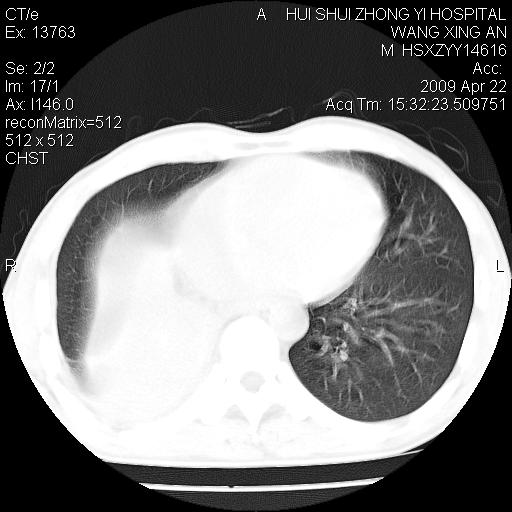

标题: CT19534:患者男、46岁咳嗽、胸痛半月。 [打印本页]

标题: CT19534:患者男、46岁咳嗽、胸痛半月。

考虑---右肺中心型肺癌继发下叶不张,少量胸水。

支持右侧中央型肺ca并右下肺不张、右侧胸腔少量积液。

1、右下肺中央型肺癌并右肺转移,右肺下叶不张。(右肺有结节影)。

2、右中上肺陈旧性肺结核(因为大多为纤维灶)。

3、右侧胸腔积液。

1、右下肺中央型肺癌并右肺转移,右肺下叶不张。(肿块围绕右肺下叶支气管生长,致管腔闭塞右肺下叶不张;右肺有结节影)。

2、右侧胸腔积液。

3、右中上肺陈旧性肺结核(右肺见纤维化病灶及点状钙化)。